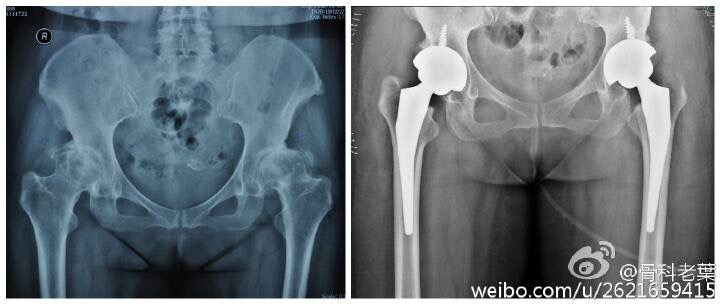

另附典型病例若干: